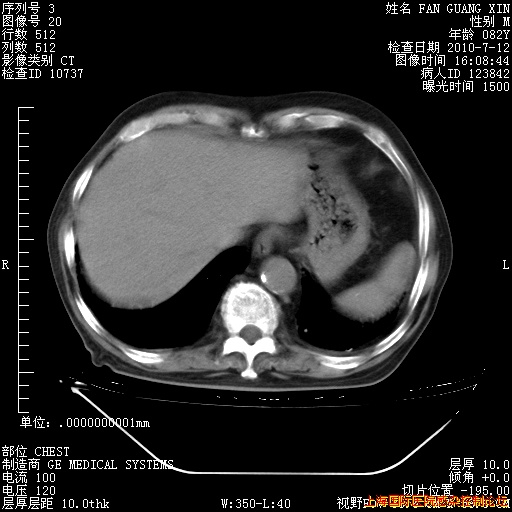

今天复查CT

今天CT

整整相隔30天的肺部CT好像有所好转啊。甲强龙减量第3天,需要观察体温。